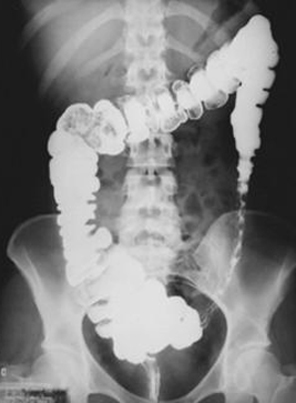

Image radiologique de lavement baryte du

colite ischemique est empreinte du doight par epaisissement

oeudemateuse des haustral du colon , image de

spasme du colon + ulceration en forme scie ou image de

stricture par fibrosis du colon .

Image radiologique de

lavement baryte du colon transverse : Image de

empreinte de pouce du colon se voyait si net au

colon transverse ( fleche rouge ) avec image

d' augementation de contraction du colon |

Image de stricture fibrosis

cu colon descendant avec image d'ulceration en forme

de scie de sa muqueuse . Lavement baryte mono de

contrast de face |